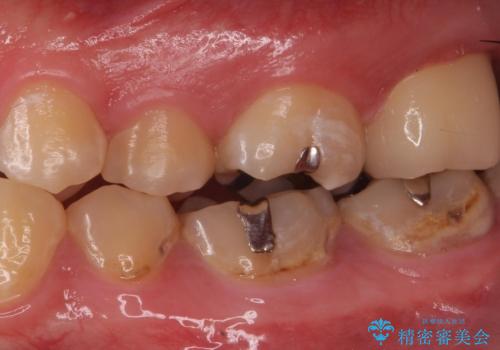

- 奥歯が欠けてしみるとのことで来院された患者様です。

かなり大きな虫歯であることと、清掃不良により歯全体が脱灰していたため、クラウンでの修復処置を行います。

奥に生えている親知らずも清掃不良であったため、今回治療する歯の清掃性を高めるために抜歯を行います。

かなり大きな虫歯でしたが症状も出ず、根管治療もせずに終えることができました。